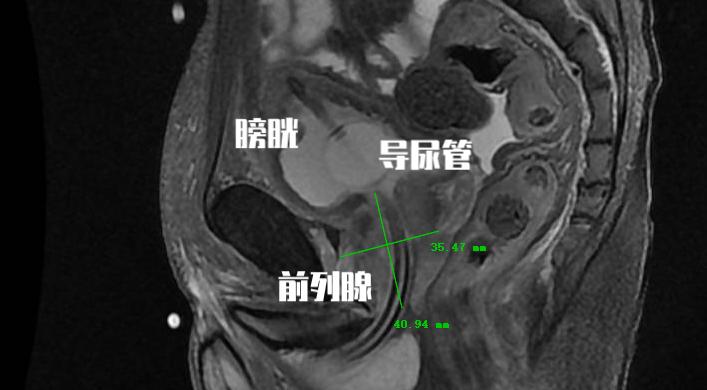

水蒸气消融手术是利用射频能量产生水蒸气储存热能,手术中将注射针插入前列腺组织,利用103度水蒸气对前列腺进行消融。 每针插入8秒产生208cal的能量,可将前列腺组织加热到70度,平均每针消融前列腺组织18g。

一般手术平均注射5针,对于大体积前列腺可注射到8~10针。随后前列腺组织将产生凝固坏死。 在术后1~3个月后,坏死的前列腺组织将逐步脱落随尿液排出,形成自然通道。

由于手术操作时间短,同时患者的疼痛及不适程度往往可以耐受。 很大一部分患者在接受这种手术方式的时候,只需要口服止痛药物就可以耐受手术。 这一点极大提高了患者的舒适性,所以很多国外的研究中心,都将这种手术放在门诊进行。